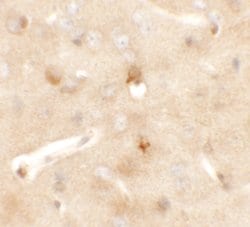

Invitrogen™ CCDC141 Polyclonal Antibody

Supplier: Invitrogen™ PA521169

Coiled-coil domain-containing protein 141 (CCDC141), also known as CAMDI, is a recently identified disrupted in schizophrenia 1 (DISC1)-binding protein that also associates with myosin II. CCDC141 preferentially associates with phosphomyosin II and causes an accumulation of phosphomyosin II at the centrosome in a DISC1-dependent manner. Knockdown of CCDC141 expression by RNAi led to severely impaired radial migration with disoriented chromosomes, suggesting that CCDC141 is required for radial migration through DISC1 and myosin II-mediated centrosome positioning during neuronal development.

| Immunohistochemistry, Western Blot | |

| An 18 amino acid peptide near the amino terminus of human CCDC141. | |

| Human, Mouse | |